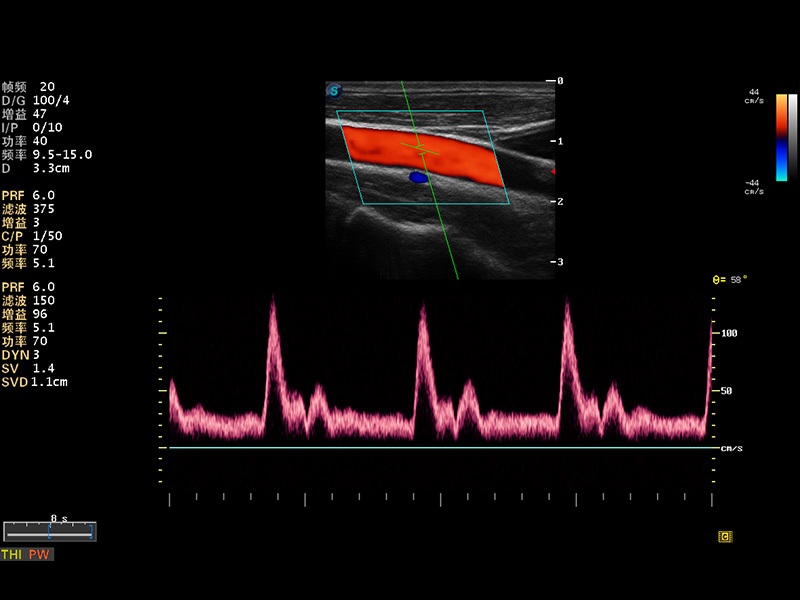

S8 EXP便携式彩色多普勒超声诊断仪是九州酷游研发的高端全身应用型便携彩超。高通道的VIS平台融合可视化(Visual)、智能化(Intelligent)和人性化(Smart)的特点,配以九州酷游自主研发生产的探头大家族,使您能够快速、准确的获得病人信息,提高工作效率的同时减轻疲劳。

μ-Scan微米成像